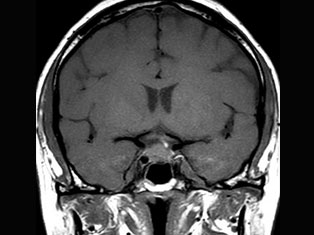

Cerebro Vascular

A stroke occurs when the blood supply to part of your brain is interrupted or reduced, preventing brain tissue from getting oxygen and nutrients. Brain cells begin to die in minutes. A stroke is a medical emergency.